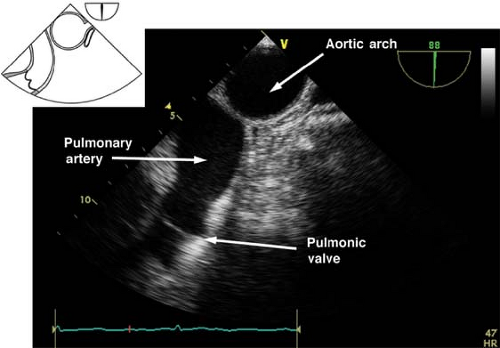

How would you obtain the Upper Esophageal Aortic Arch SAX View?

Insert the probe to the ME, sector depth 10-12cm, angle 0°

Find the ME Descending Aorta SAX (0°) view

Withdraw the probe to obtain the UE Aortic Arch LAX (0°) view

Rotate the omniplane angle to 60-90°

Bring the pulmonic valve and pulmonary artery in view